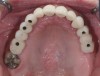

Fig 13. Short implants used to avoid grafting. Fig 13: Occlusal view of a full-arch fixed dental prosthesis supported by five endosseous

implants placed. Fig 14: The left distal implant was tilted to support the left molar unit of the prosthesis. Fig 15: A 6 mm x 5.4 mm implant

was used to support the right molar unit of the prosthesis. The strategic application of nongrafted solutions helped accelerate treatment and

reduce treatment costs.

Fig 14. Short implants used to avoid grafting. Fig 13: Occlusal view of a full-arch fixed dental prosthesis supported by five endosseous